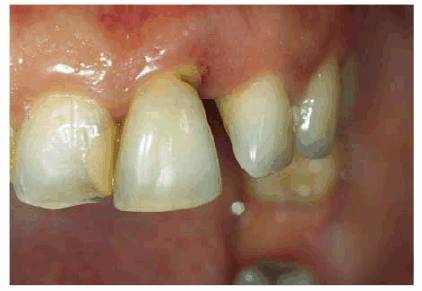

patient (Figures 17-1A to

C

Figure 17-1A to C: These photographs illustrate the complex dental condition of a 71-year-old male: (A) The palatal cervical regions of the maxillary anterior teeth exhibit sharp, wedge-like lesions that are characteristic of abfraction. These areas would be difficult, if not impossible, to have resulted from toothbrush abrasion. (B) The buccal aspects of the maxillary posterior teeth show smooth, concave configurations that are consistent with toothbrush abrasion and/or erosion. (C) The buccal surfaces of the mandibular teeth have lesions that possess components of both abfraction (sharp margins in the occlusal regions) and abrasion (concave geometry and gingival recession in the cervical regions).